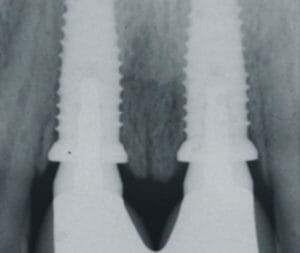

Dental implants are so successful because they are made of high-grade titanium metal. The human bone fancies titanium so much that it grows onto it as if it’s made of the same material. “Dental implants should last you your lifetime,” Dr. Aires explained. “Once the bone attaches onto the titanium, it becomes a permanent part of the body and very unlikely that it would breakdown.”

People often assume that the dental implant includes the actual tooth, but this is not the case. The implants are essentially the roots securing new teeth in place. A tooth made of ceramic or Zirconia is attached onto the implant.